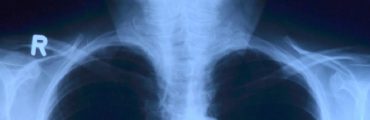

Si la montée en puissance de l'intelligence artificielle générative peut inquiéter, elle est accueillie dans le corps médical pour ses multiples applications. Interprétation d'images médicales, traitement de données en masse selon d'innombrables critères... différents outils reposant sur une IA apportent un soutien aux gestes médicaux, dans un contexte où un rythme déjà soutenu s'accélère.